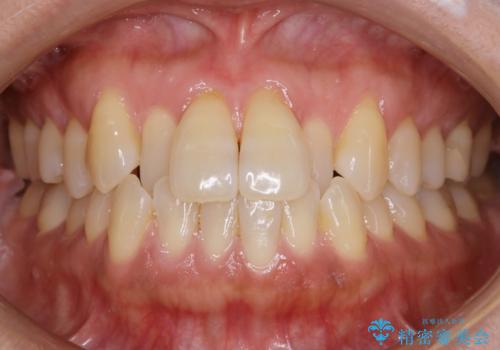

デコボコと変色した前歯 抜歯矯正と審美歯科治療